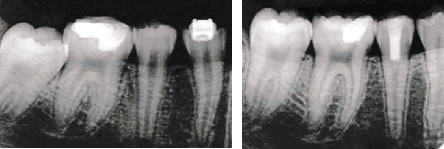

虫歯が進行して歯の神経のまで達してしまったら従来は神経を取る治療しか手段がありませんでした。しかし、近年開発されたMTAセメントとよばれる新しい虫歯治療材料で、必ずしも歯の神経を取らなくても治せる可能性が生まれました。当院では患者様の歯の神経を極力取らない治療法でむし歯治療を行っております。

上記のように、MTAセメントとプラズマ殺菌を併用することによって歯髄の全部もしくは一部を残すことができます。歯は歯髄を全部取ると枯れ木のようにもろくなる為、内部を補強して被せていかなければならなくなります。

MTAにより象牙質が出来ていて神経を残すことによって歯の寿命は長くなります。